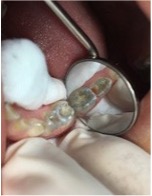

Transcurridos dos años del último control, aún con la dentición primaria completa, los dientes estaban más claros y había algunas áreas de completa despigmentación en la superficie oclusal de los molares. En el examen clínico intraoral, se detectaron las primeras lesiones de caries, en la distal del 74 y oclusal del 75; en el diario de alimentación se observó mayor frecuencia de alimentos cariogénicos. Se observó durante la remoción de la lesión de caries que el pigmento estaba más impregnado en la superficie del esmalte. A los 6 años, emergió el primer diente permanente, siendo el incisivo central inferior del lado izquierdo, diente 31, con su coloración normal, seguido del diente 41 (Figuras 6 a 9). El primer molar permanente inferior izquierdo (36) también emergió totalmente libre de pigmentos, sin embargo, la cúspide mesiovestibular del primer molar permanente derecho (46) presentó ligera coloración verdosa (Figura 10B y 11). En el último control a los 4 años se observó la presencia de incisivos permanentes superiores e inferiores emergidos sin pigmentación verdosa (Figura 12).

Figura 8: Control de 2 años. Hemiarcada izquierda. Dientes 74 y 75 con pigmentación verde en la dentición y lesión de caries. Lesión de caries del 74,75